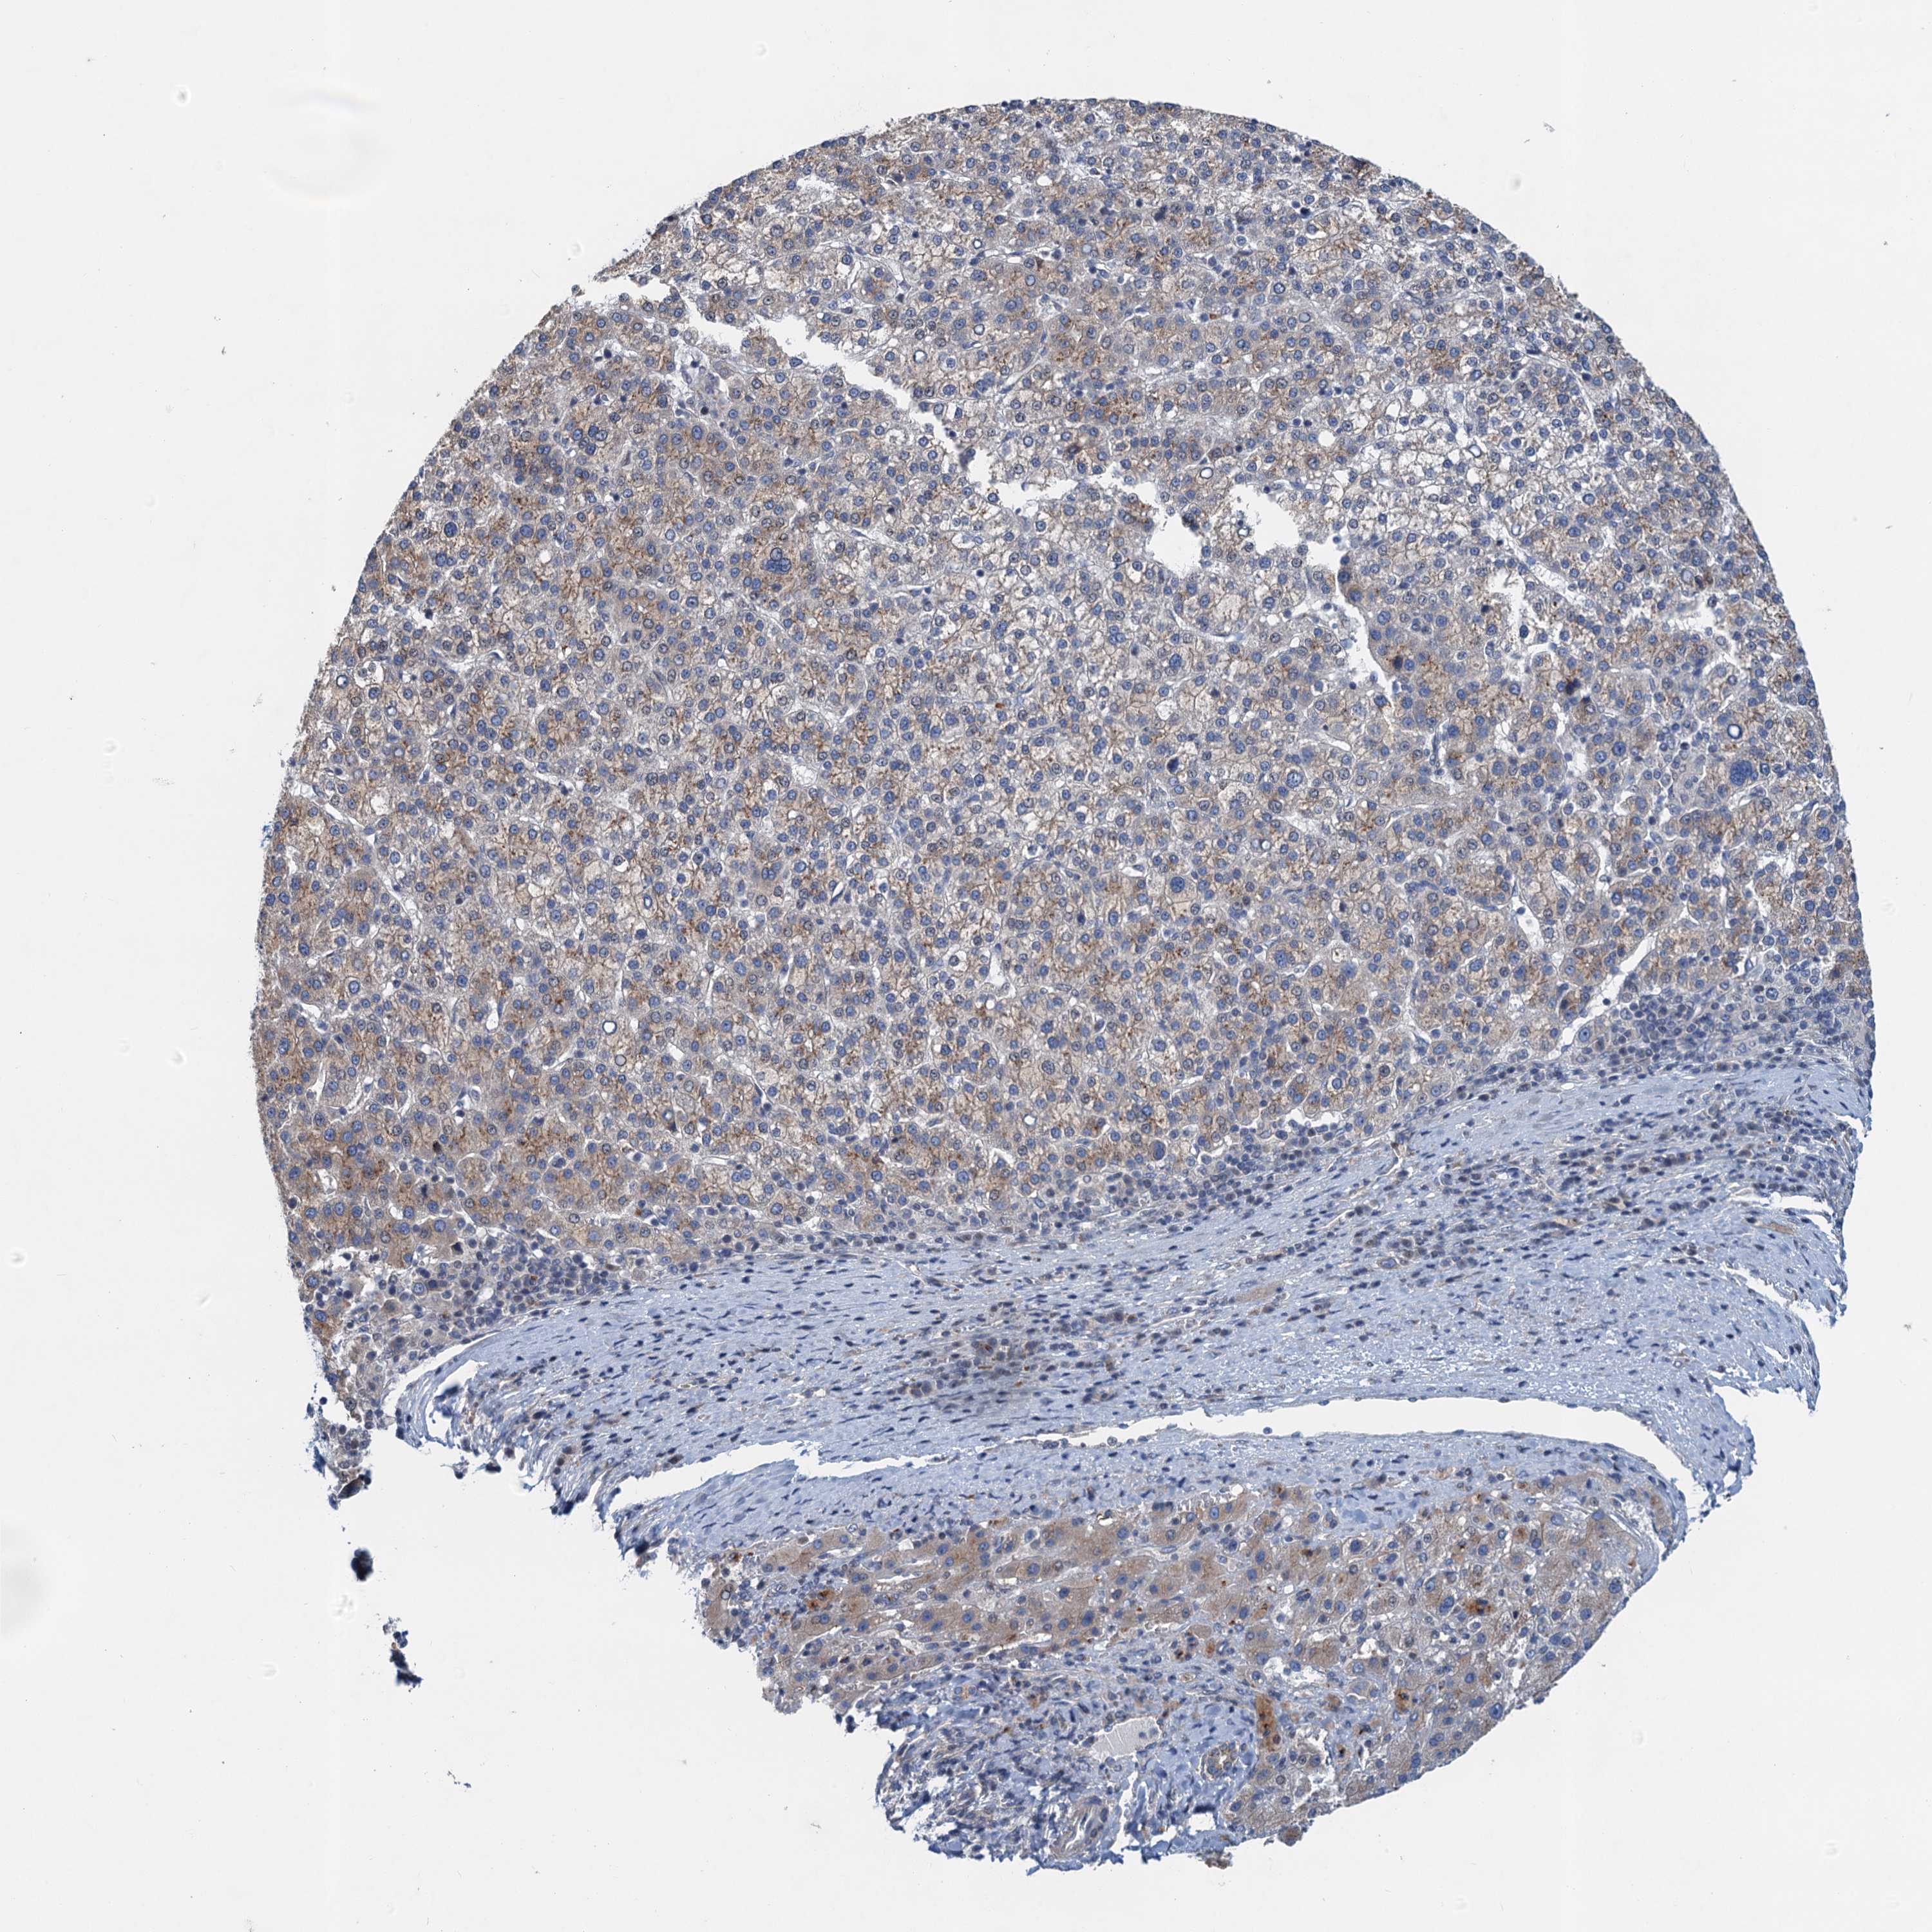

LIVER CANCER - Protein expressioni

A mouse-over function shows sample information and annotation data. Click on an image to view it in a full screen mode. Samples can be filtered based on level of antibody staining by selecting one or several of the following categories: high, medium, low and not detected. The assay and annotation is described here.

Note that samples used for immunohistochemistry by the Human Protein Atlas do not correspond to samples in the TCGA dataset.

Antibody stainingi

Antibody staining in the annotated cell types in the current human tissue is reported as not detected, low, medium, or high, based on conventional immunohistochemistry profiling in selected tissues. This score is based on the combination of the staining intensity and fraction of stained cells.

Each image is clickable and will lead to virtual microscopy that enables deeper exploration of all samples and also displays staining intensity scores, fraction scores and subcellular localization as well as patient and tissue information for each sample.

Antibody HPA039730

Antibody HPA040385

Staining

High

Medium

Low

Not detected

Intensity

Strong

Moderate

Weak

Negative

Quantity

>75%

75%-25%

<25%

None

Location

Nuclear

Cytoplasmic/membranous

Cytoplasmic/membranous,nuclear

Cholangiocarcinoma

Carcinoma, Hepatocellular, NOS